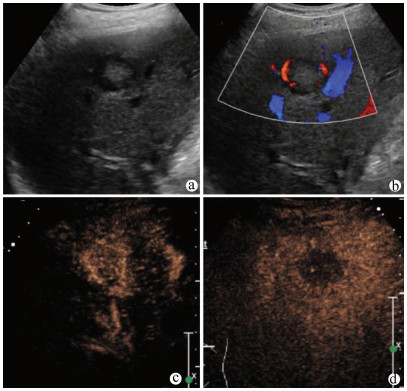

肝病超声诊断指南

中华医学会超声医学分会, 中国研究型医院学会肿瘤介入专业委员会, 国家卫生和健康委员会能力建设和继续教育中心超声医学专家委员会

2021, 37(8): 1770-1785. DOI: 10.3969/j.issn.1001-5256.2021.08.007

摘要(3068) HTML (6587) PDF (9311KB)(804)

超声检查无创、实时、价廉,无辐射、便于反复进行,是最常用的肝脏影像学检查方法。近年来,超声检查新技术如超声造影、弹性成像发展迅速,可有效鉴别肝内占位性病变性质、评估肝纤维化和门静脉高压程度以及监测肝病治疗效果,在临床肝病及其介入治疗中发挥重要诊断价值。本指南规范了肝病多模态超声技术(灰阶超声、彩色多普勒超声、超声造影、弹性超声)检查的仪器调置、患者准备及医生检查方法;对肝脏弥漫性病变(炎性病变、纤维化、硬化)、多种占位性病变及肝病介入操作的多模态超声技术诊断标准进行了定义和规范,同时推荐了超声监测周期及肝脏疾病超声诊断报告书写规范。